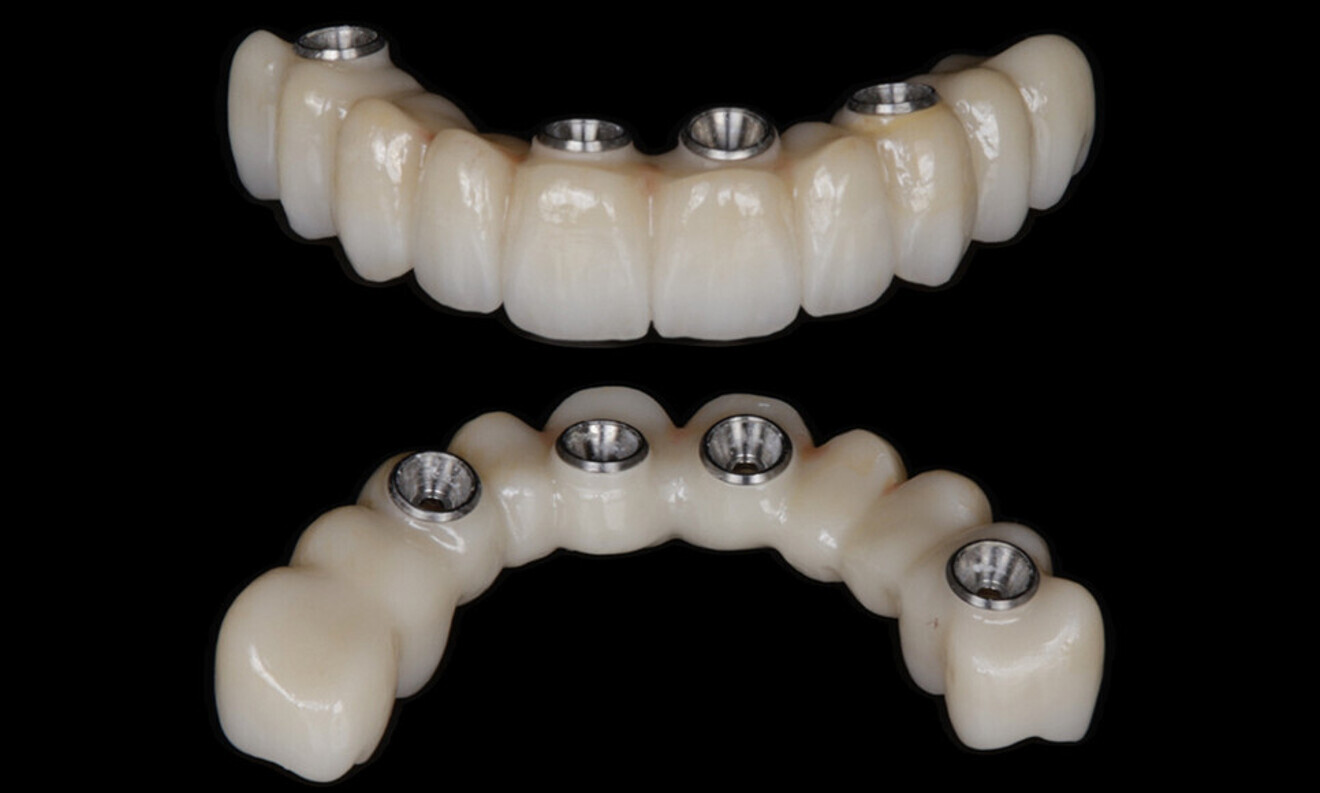

After a healing period of five months and successful osseointegration, the process for the definitive restorations was initiated. The chosen material was milled monolithic zirconia, and Variobase final abutments was used, placed on the screw-retained abutments to ensure excellent stability and retention of the definitive restorations (Figs. 69–75).

Figs. 69–75: The definitive restorations were fabricated after a five-month healing period

The soft tissue was in good condition, and the definitive restorations were placed (Figs. 76 & 77). After placing the definitive restorations, oral hygiene instructions were given to ensure proper care and prevent complications. Additionally, the occlusion was carefully checked and adjusted as needed (Figs. 78–83).

definitive prosthetic rehabilitation of the maxillary and mandibular arches with screw-retained implant-supported restorations.